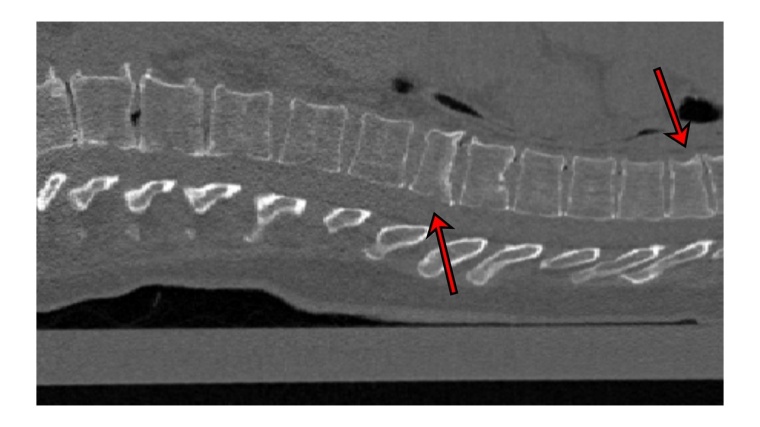

Forschende der Uni Kiel haben eine Software entwickelt, die Wirbelbrüche auf CT-Bildern automatisch erkennt und prognostisch bewertet.

Oft werden CT-Bilder vom Brustkorb aufgenommen, um zum Beispiel die Lunge anzuschauen. Die Wirbelsäule ist zwar auf dem Bild zu sehen, wird aber nicht geprüft, weil ein anderes Problem im Vordergrund steht. „Unser Programm kann bei solchen Untersuchungen im Hintergrund laufen. Es schaut sich automatisch die Wirbelsäule an und gibt einen Hinweis auf Frakturen der Wirbelkörper, die ansonsten vielleicht nicht entdeckt worden wären“, erklärt Erstautor Yilmaz. Das ist wichtig, denn das Vorhandensein von Wirbelfrakturen erhöht das Risiko weiterer Brüche erheblich. Die Software arbeitet mit neuronalen Netzen. An 159 CT-Bildern der Wirbelsäule, die aus sieben Krankenhäusern Deutschlands stammten, wurde die KI getestet. Erfahrene Radiologen begutachteten zuvor die Bilder und entdeckten 170 Frakturen. „90 Prozent der Fälle mit Frakturen klassifizierte das neuronale Netz korrekt sowie 87 Prozent der Wirbel ohne Frakturen“, berichtet Yilmaz.

Darüber hinaus kann das Programm aber nicht nur Brüche erkennen, sondern auch zwischen milden Frakturen (Grad 1) und schwereren (Grad 2 oder höher) unterscheiden. „Diese Diagnostik ist für Abschätzung der zukünftigen Frakturrisikos entscheidend“, so Yilmaz. Dies gelte insbesondere auch für Hüftfrakturen, die gerade im Alter mit hoher Einschränkung von Lebensqualität und erhöhter Sterblichkeit einhergehen. „Wir entwickeln somit ein Frühwarnsystem zur Prävention schwerwiegender Konsequenzen von Osteoporose“. Für den generellen Einsatz in der Klinik ist die Technik noch nicht verfügbar. Sie soll aber in absehbarer Zeit zumindest für Forschungszwecke eingesetzt werden können.